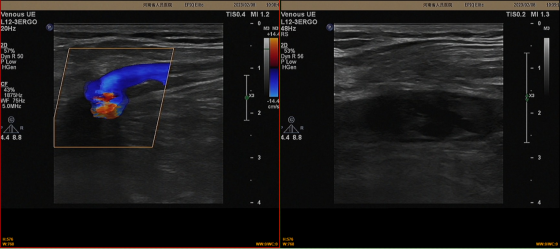

在河南省人民医院呼吸与危重症医学科门诊,齐咏主任接诊查体:呼吸平稳,心肺查体无异常,双下肢无水肿,腿围无差异。考虑到患者前期有新型冠状病毒感染(COVID-19)病史,但该患者确诊新型冠状病毒感染(COVID-19)的时间已大于1个月,仍有气短、发热,不能用肺炎解释。且患者下肢疼痛出现在单侧下肢,尽管双下肢腿围并无差别,仍需警惕深静脉血栓的存在。随即给患者安排了凝血六项和双下肢血管彩超的检查。D-二聚体1.51μg/ml明显增高,彩超提示左侧下肢多个静脉血管均有血栓形成。

患者双下肢血管彩超提示有股静脉血栓,而存在股静脉血栓是十分危险的,其一旦脱落,有可能会导致患者出现致命性的肺栓塞,在短时间内,患者就会出现生命的危险。